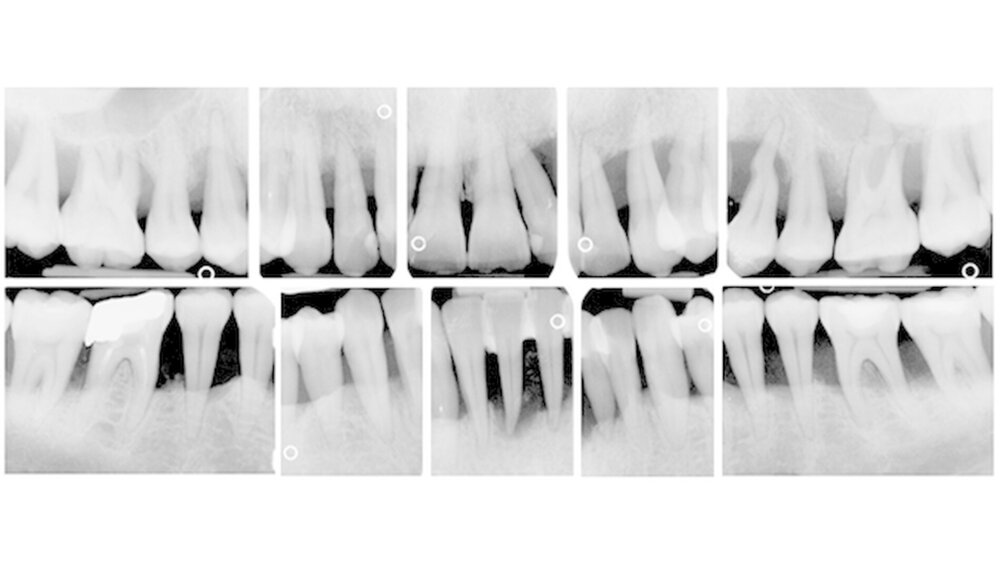

Während für die chronische Parodontitis (ChP) Langzeitergebnisse nach Therapie über zehn und mehr Jahre vorliegen [Faggion et al. 2007, Eickholz et al. 2008], wurden bisher keine Langzeitdaten über diesen Zeitraum für Patienten mit aggressiver Parodontitis (AgP) erhoben.

Daher war das Ziel der vorliegenden Studienreihe, Zahnverlust, Auftreten von Rezidiven und Kariesinzidenz über zehn Jahre nach Therapie bei Patienten mit AgP zu untersuchen sowie mögliche Risikofaktoren zu identifizieren, um die Prognosestellung und somit auch Therapieentscheidungen bei diesen Patienten auf eine breitere Basis zu stellen.

Im Rahmen der Untersuchungen konnten wir zeigen, dass Patienten mit AgP nicht nur kurzfristig, sondern auch über zehn Jahre nach APT stabile parodontale Verhältnisse vorweisen. Mit einer Zahnverlustrate von 0,13 Zähnen/Patient/Jahr und einer 10-Jahres-Überlebensrate von 94,8 Prozent tritt Zahnverlust insgesamt selten bei Patienten mit AgP auf und unterscheidet sich nicht von Zahnverlusten bei Patienten mit ChP. Mehr als 50 Prozent der Probanden erlitten keinen Zahnverlust und nur wenige verloren mehr als drei Zähne.

Zahnverlust tritt demnach auch bei der AgP vor allem bei sogenannten Hochrisikopatienten auf. Auf Patientenebene konnten die Faktoren niedriger Ausbildungsstand, Alter und Abwesenheit des IL-1-Polymorphismus als signifikante Risikofaktoren für Zahnverlust festgestellt werden. Signifikante zahnbezogene Faktoren für Zahnverlust stellten die Punkte hoher initialer Knochenabbau, Lokalisation im Oberkiefer, Zahntyp ‚Molar’ und Pfeilerzahn dar.

Bei etwa einem Viertel der Patienten lag bei Reevaluation ein Rezidiv vor. Als Risikofaktoren für das Auftreten eines Rezidivs konnten Rauchen, ein hoher mittlerer Gingival Bleeding Index (Ainamo & Bay 1975) und hohe nachweisbare Mengen der Parodontalpathogene T. forsythia und T. denticola festgehalten werden. Patienten, die regelmäßig zur UPT erschienen waren hingegen vor Rezidiven geschützt. Ebenso zeigte die Compliance zur UPT einen signifikant positiven Einfluss auf die Kariesinzidenz.